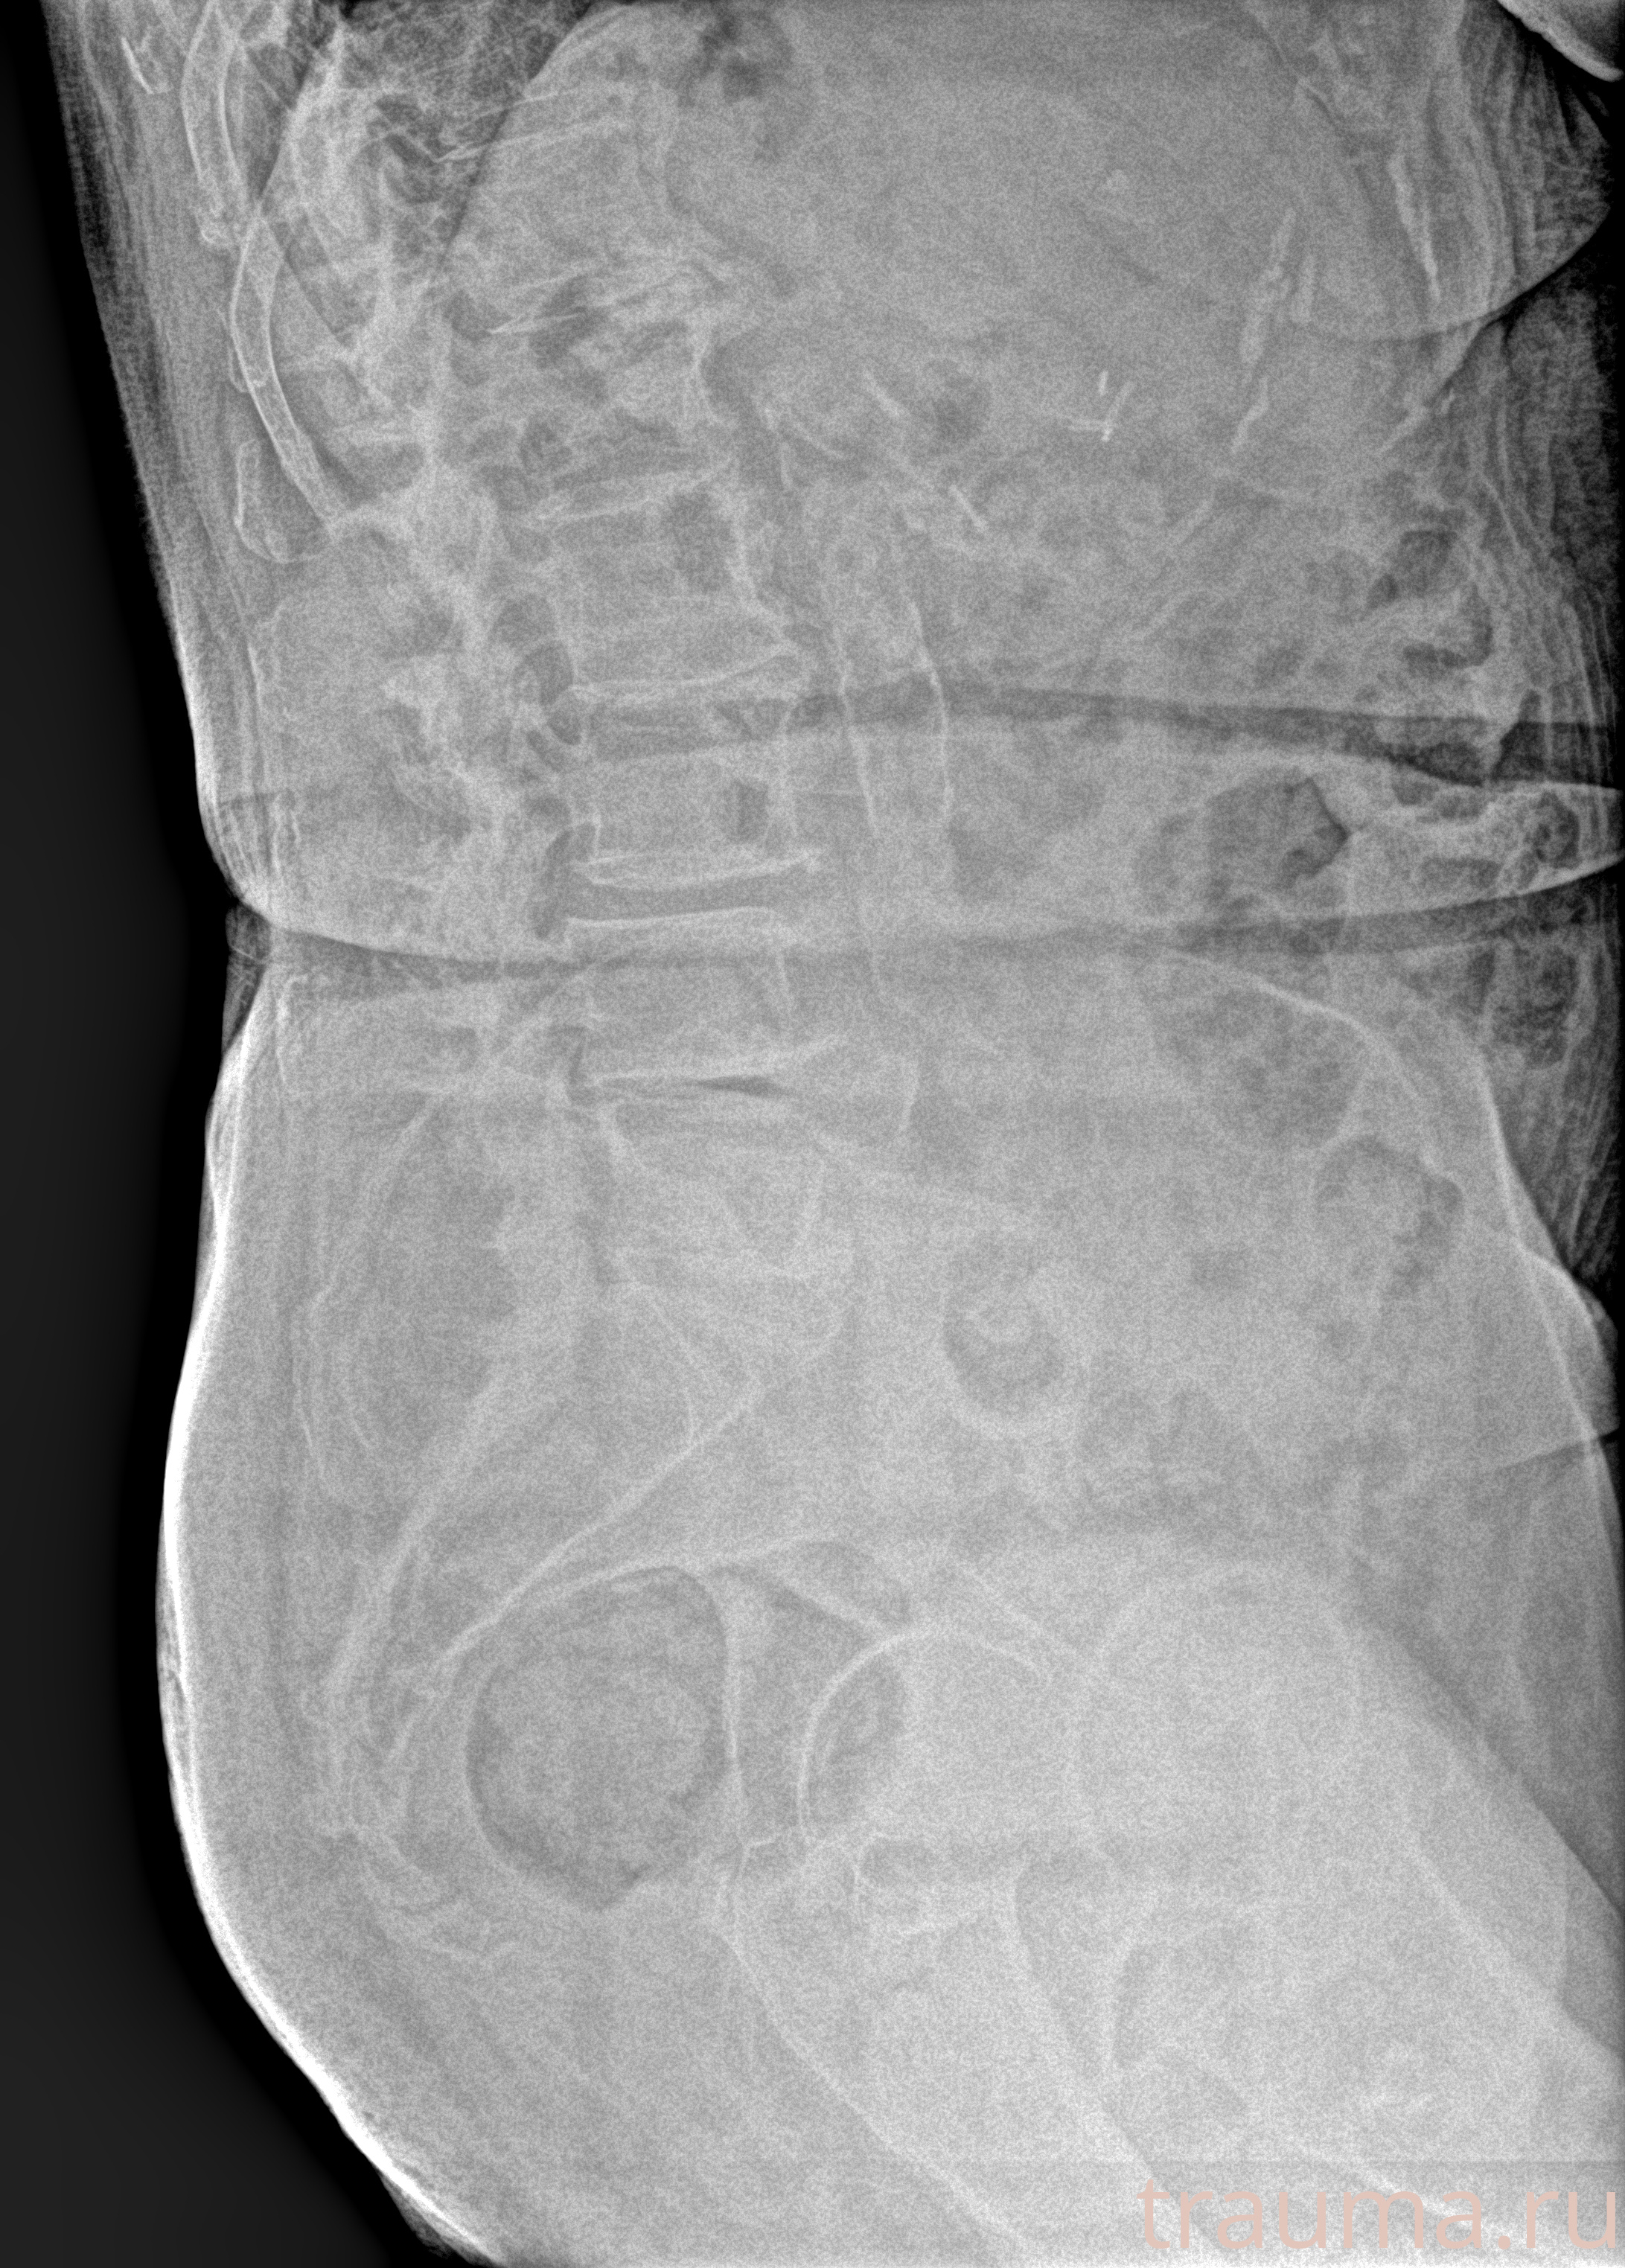

Рентген на дому: по вашему адресу приезжает врач-рентгенолог, травматолог-ортопед с мобильным рентгеновским аппаратом, проводит диагностику травмы или заболевания, делает необходимые рентгенограммы, дает рекомендации по дальнейшему лечению. Получить качественные снимки в домашних условиях возможно благодаря уникальной методике, разработанной МосРентген Центром для института  Склифосовского

при переломе шейки бедра и пневмонии от компании МосРентген Центр - партнера Института имени Склифосовского